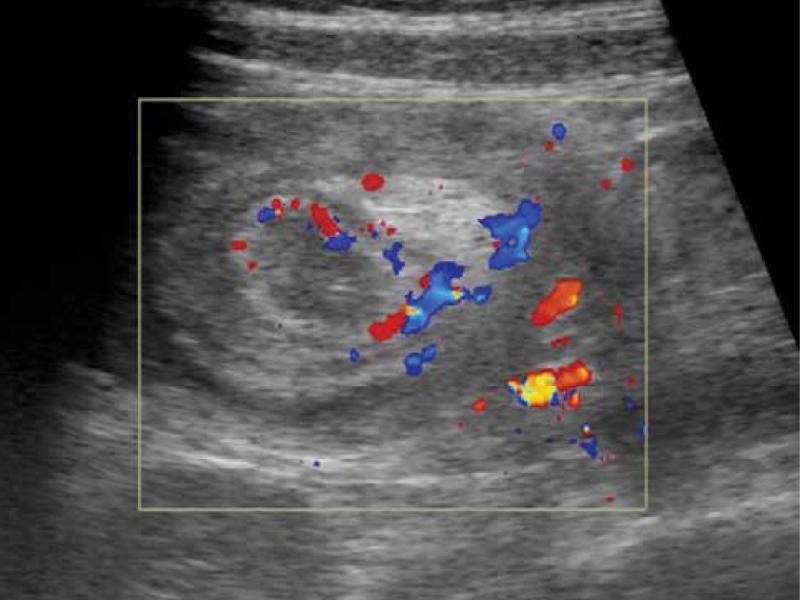

Fig. 4.

Colour Doppler ultrasound image in the axial plane showing intact vascularity in the bowel wall within the intussusception